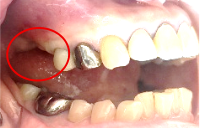

男性 Yさん 60代 (インプラント)

主訴

右下の奥歯の歯肉が痛い。時々血が出たり、腫れたりする。

治療内容

右下のブリッジの支台になっている前方の歯が、歯根破折を起こしていましたので抜歯しました。インプラントを右下第一、第二大臼歯部に2本埋入しました。

所感

実はこの患者さんは、2014年に右下の第二大臼歯(一番奥の歯から2番目の歯)を歯根破折により抜歯し、その際の治療法としてブリッジを選択されました。そして今回、ブリッジを支えていた歯(第一大臼歯)がついに歯根破折を起こしてしまいました。

ブリッジは、3本分の歯を2本の歯で支えるため、支える歯の負担が大きくなり、歯根破折を起こす危険性が高くなります。

今回の抜歯後は、歯が2本ない状態になるので、そこを補う方法についてご説明しました。選択肢は再度ブリッジを入れるか、インプラントになります。ブリッジにして支える歯がまた折れてしまうと歯が3本ない状態になる可能性があるため、インプラントを選択されました。もし11年前にブリッジではなくインプラントを選んでおられたら、今回の歯根破折や抜歯は起きなかったかもしれません。ブリッジは、噛む力の強い方、歯ぎしりをする方、硬い食べ物が好きな方は、支えの歯の負担がより大きくなるのでおすすめできません。

インプラントは、それ自身が単独で植立しているので、他の歯に負担がかかりません。インプラントは、欠損を補う最良の方法と考えます。

インプラント2本:¥726,000(税込)

Before

抜いた歯 真二つにわれています

After